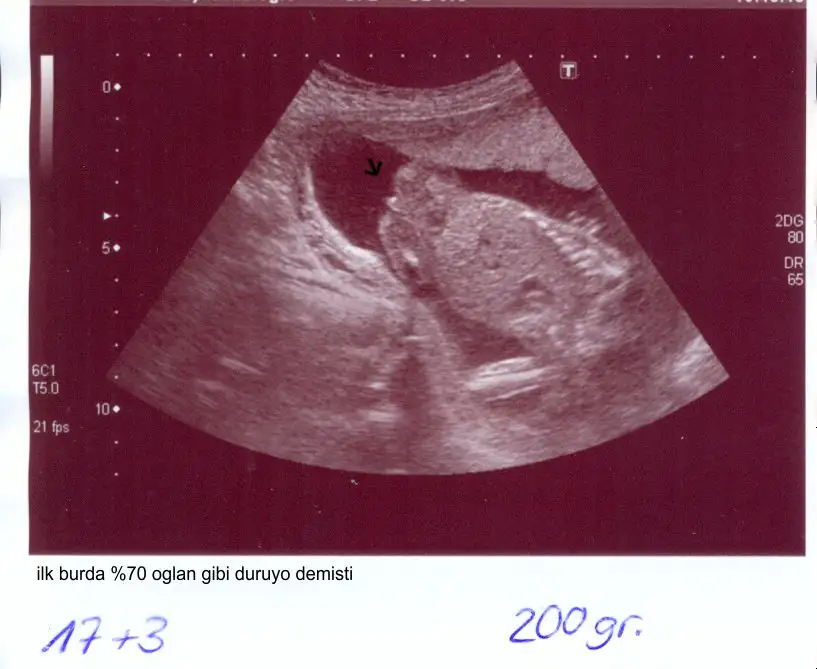

sumruuu cnm bu pipiye benzemiyoki cnm benim,dün gördüm yine ben oğlumun pipisini uyyy kurban olsun annesi oğluşuna.benim usg mi bi koysamda görsen ama bilmiyomki nasıl yükleniyo.

canim valla bilmiyorum iste doktor öyle diyordu ta gecen haftaya kadar. gecen hafta kiz olabilir dedi iste pazartesi gittigim doktorda bana före kiz dedi. hayirlisi olsun canim. sagliklica kucagima alayimda kiz erkek fark etmez. ama sen biliyorsundur yani. pipiye benzemiyo diyorsan ozaman ben kiza iyice bi alisayim. 30 hafta erkege alismistik simdi son 10 hafta kiz beklemek tuhaf. neyse allahim hepimize yavrularimiuzi sag salim kucagimiza almayi nasip etsin.